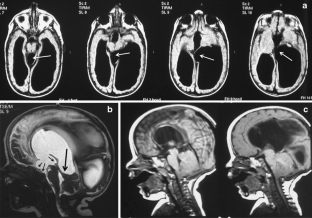

The sylvian aqueduct is the most common site of intraventricular blockage of the cerebro-spinal fluid. Clinical aspects, neuroradiological appearance, and treatment of hydrocephalus secondary to aqueductal stenosis are specific.

The correct interpretation of the modern neuroradiologic techniques may help in selecting adequate treatment between the two main options (third ventriculostomy or shunting). In the last decades, endoscopic third ventriculostomy has become the first-line treatment of aqueductal stenosis; however, some issues, such as the cause of failures in well selected patients, long-term outcome in infant treated with ETV, and effect of persistent ventriculomegaly on neuropsychological developmental, remain unanswered.